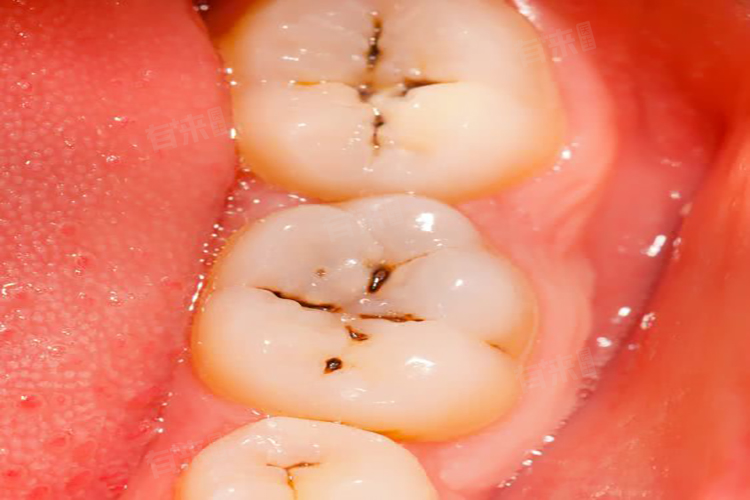

窝沟黑线是指牙齿咬合面窝沟处出现的黑色线性痕迹,多因色素沉积或早期釉质脱矿引起。医生判断无需补牙,主要基于窝沟黑线的性质和牙齿损伤程度,相关原因包括色素沉着、窝沟形态导致的视觉假象、早期釉质脱矿未累及牙本质、临床检查无实质性缺损等。

1、色素沉着:长期食用深色食物、饮用咖啡、浓茶或吸烟,色素会沉积在窝沟内,形成黑色线条。这种情况下,牙釉质结构完整,无脱矿或龋坏,仅为表面着色,无需通过补牙干预。

2、窝沟形态导致的视觉假象:牙齿窝沟本身较深且狭窄,光线照射时可能产生阴影,使窝沟看起来呈黑色。这种情况下,窝沟内壁的釉质结构正常,无实质性缺损,医生通过探针检查无卡住感,因此无需进行补牙操作。

3、早期釉质脱矿未累及牙本质:当窝沟处釉质出现轻度脱矿时,可能呈现白垩色或黑色改变,但脱矿范围局限于釉质表层,未穿透釉质到达牙本质。此时牙齿尚未形成龋洞,通过加强口腔卫生和促进釉质再矿化即可改善,无需补牙。

4、临床检查无实质性缺损:医生通过口腔检查、X线片等手段判断窝沟黑线处是否存在牙体组织缺损。若探针无法探及粗糙面或龋洞,且X线片显示釉质层完整,则说明黑线未发展为龋齿,无需补牙。